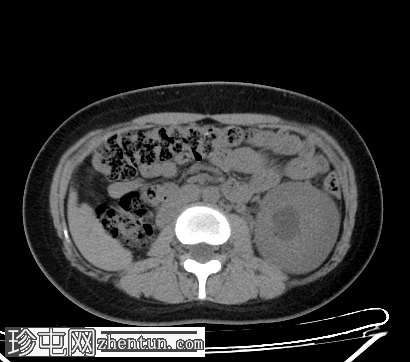

CT扫描

轴向扫描

非造影

腹部CT平扫和造影扫描显示左肾实质增大,伴I级肾积水,右肾在肾窝内未见异常。双子宫完整(两个子宫体和两个宫颈),阴道隔膜将阴道分成两半,阴道右半部分积液,非造影片上积液密度较大,提示为

血液

(阴道积血)。

增强扫描图像提示存在一条血管分支压迫左肾盂-输尿管连接处,导致肾积水。

道格拉斯囊内有少量游离液体。

右侧卵巢可见黄体。

其他腹部器官未见异常。

CT和MRI检查结果为Herlyn-Werner-Wunderlich综合征的典型表现,其特征为经典的三联征:III型苗勒氏管异常(完全性双子宫)、中肾管异常(肾发育不全)以及肾发育不全侧阴道积血。

该患者左肾积水是偶然发现的,且无任何明确的梗阻原因,例如泌尿系统结石、

肿瘤

或炎症。积水延伸至左肾盂-输尿管连接处,疑似存在血管分支交叉,该分支可能造成压迫,从而导致肾积水。